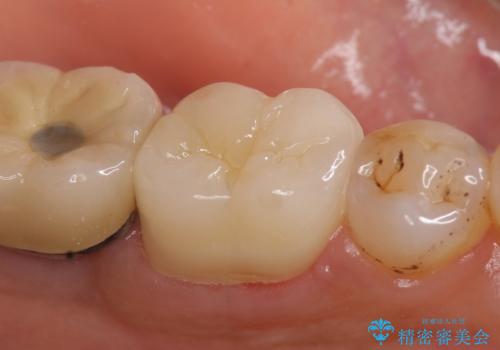

その後症状の消失を確認後、オールセラミッククラウンによる補綴を行いました。

今回用いたオールセラミッククラウンはジルコニアフレームという白い素材の上にセラミックを盛っているため、審美性が非常に高いのが特徴です。

また、ジルコニアは人工ダイヤモンドの材料にも使われているほど高い強度を持っており、そのためオールセラミッククラウンは審美性だけでなく、奥歯やブリッジの補綴も可能とするクラウンです。